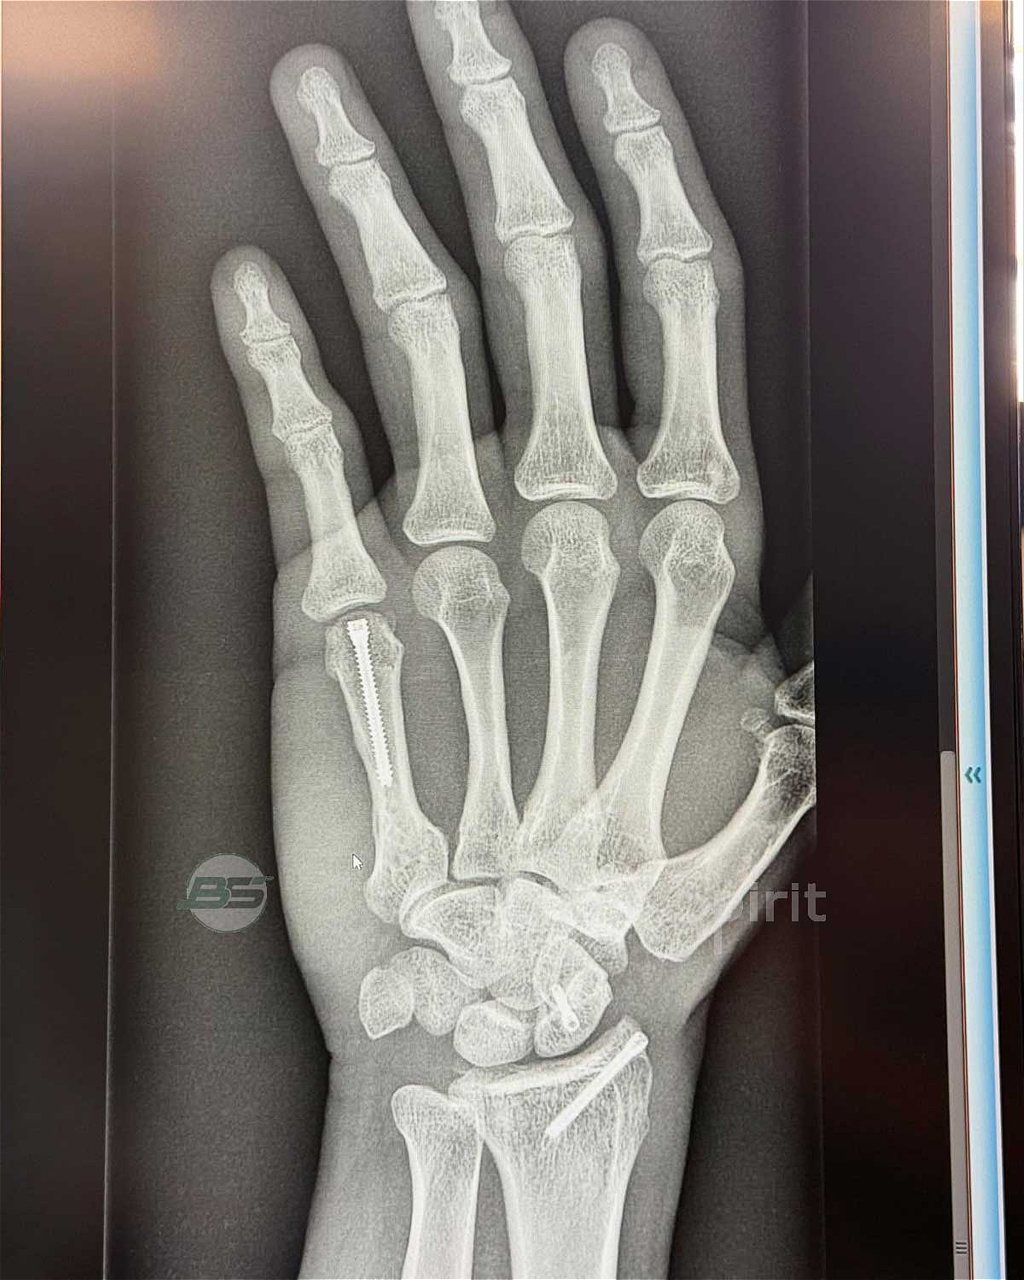

Ο Jorge Martin βρίσκεται σε διαδικασία ανάρρωσης, μετα τον τραυματισμό του από μια άσχημη πτώση την πρώτης ημέρα της επίσημης και προτελευταίας presession δοκιμής στο Sepang.

Αυτός ο τραυματισμός του στέρησε την ευκαιρία να λάβει μέρος στην τελευταία δοκιμή στο Buriram, ενώ τώρα προσπαθεί να αναρρώσει γρήγορα με την ελπίδα να είναι στο Buriram σε καλή κατάσταση για τον πρώτο αγώνα GP της σεζόν με το N° 1 στην μοτοσυκλέτα του.

Ο Ισπανός, ανυπομονεί να βρεθεί ξανά στην πίστα, και όπως γράφει στο Instagram μαζί με τις φωτογραφίες που δημοσίευσέ: «Εδώ βλέπετε τη ζωή μου τελευταία ενώ αναρρώνω από το ατύχημα του Sepang και προσπαθώ να είμαι σε θέση να οδηγήσω στο Ταϊλανδέζικο GP! Παμεεε»